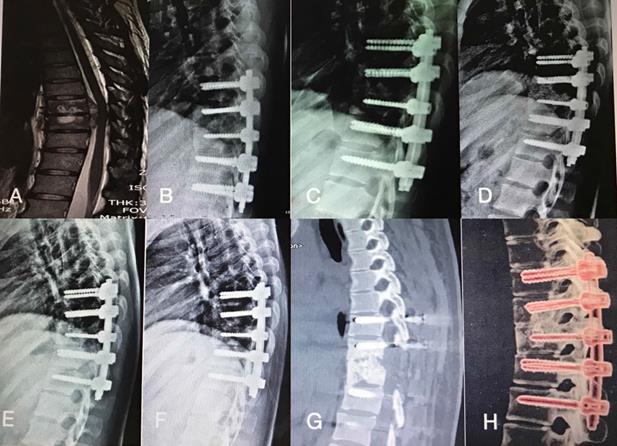

Figure 3

A 45-year-old man with thoracic spinal tuberculosis (T9-10)underwent single-segment posterior debridement and decompression combined with internal fixation. (A)Pretreatment MRI showing the destruction of the T9-10vertebrae and concomitant compression of the spinal cord. (B,C,D,E) Immediate, 3-month, 6-month, 1-year, 2-year postoperative X-ray demonstrated good location of bone graft and internal fixation. (F,G,H) At the 36-month follow-up, plain X-ray and CT showed maintenance of the correction and solid fusion.

The thoracic spinal TB was well cured and the bony fusion at a mean time 12.90±3.91 months in group A was longer than that in group B (6.75±1.55 months) and group C (5.52±1.64 months) (P<0.05) (Figures 2 & 3). No significant difference was found at the mean segmental angle, mean intervetebral height of preoperation and final FU among the groups (P>0.05).